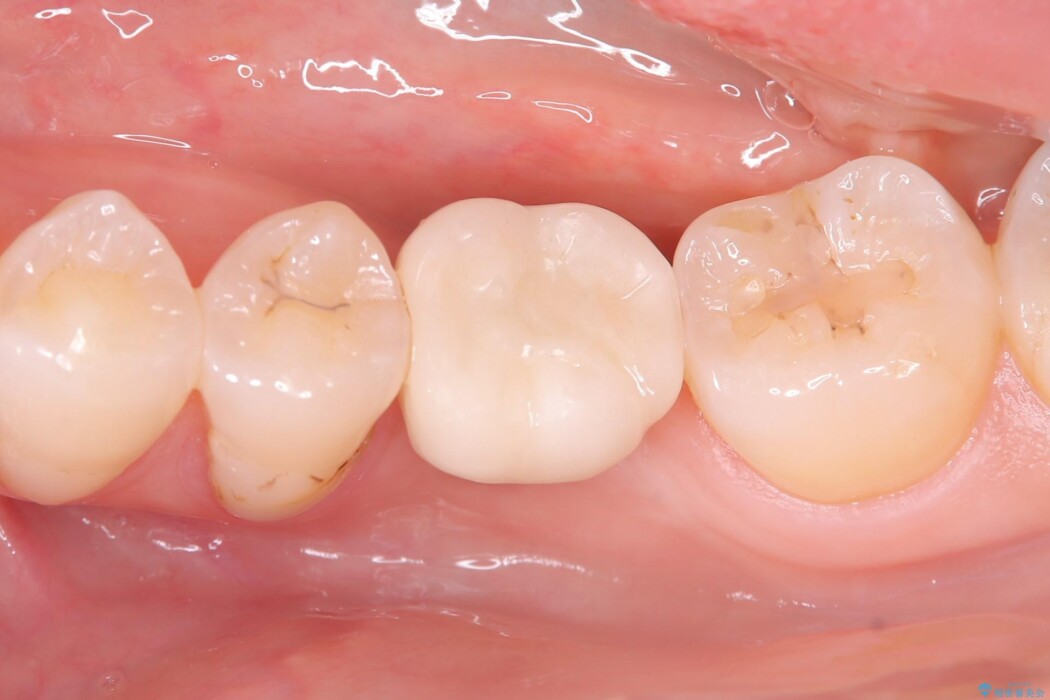

一般的に、骨が少ない場所への埋入は高度な技術を要しますが、今回は適切なサイズ(8.5mm)を選択し、埋入する深さを緻密にコントロールすることで、周囲の神経や重要な組織を傷つけることなく安全に処置を完了しました。

現在はインプラントが骨としっかり結合し、被せ物を装着して力強く噛めるようになっています。長期間の放置によって低下していた咀嚼機能が回復し、「もっと早く相談すればよかった」と喜んでいただけました。